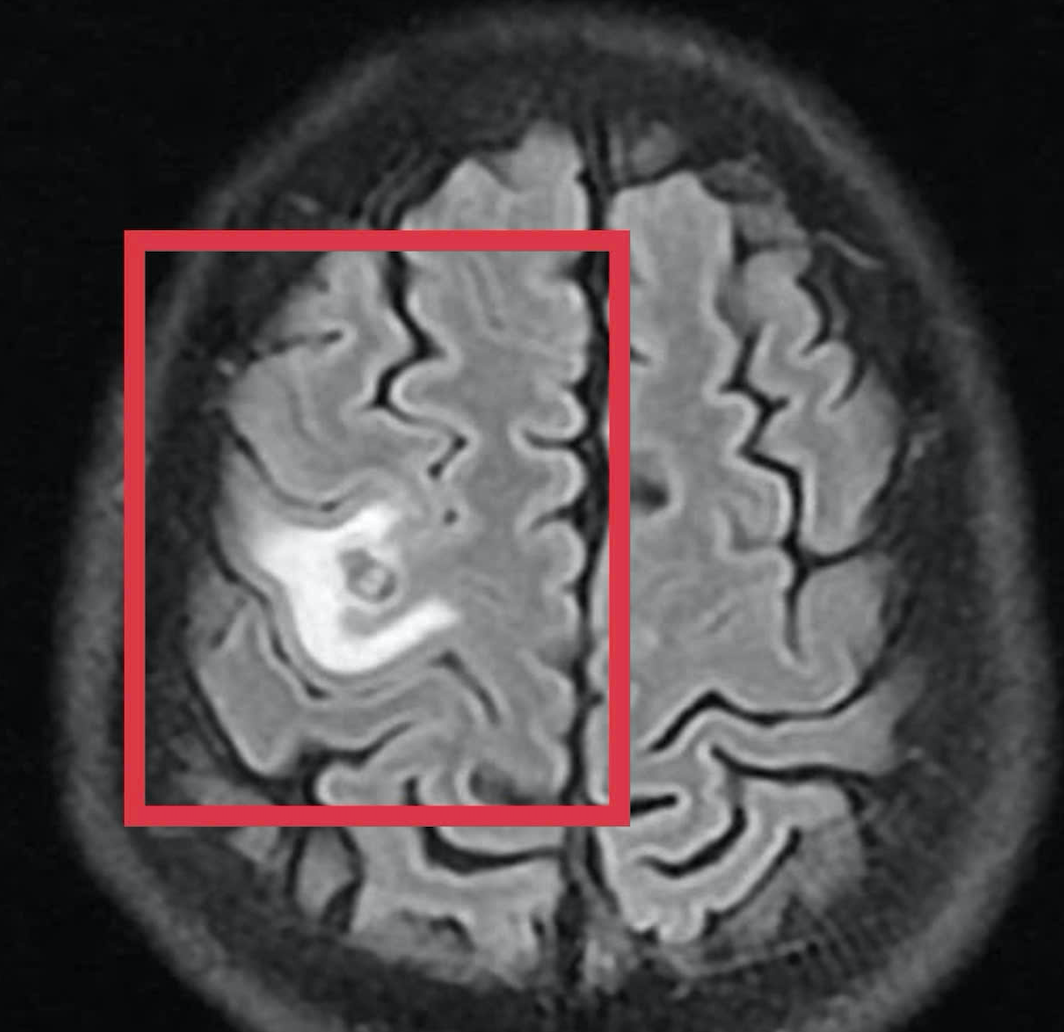

Hình ảnh tổn thương não của bệnh nhân.

Kết quả chụp cộng hưởng từ (MRI) sọ não cho thấy một tổn thương dạng nang nhỏ tại thùy trán trái, kích thước khoảng 11 x 7 mm, xung quanh có phù não nhẹ. Hình ảnh này không điển hình cho u não nguyên phát mà hướng nhiều hơn đến tổn thương do ký sinh trùng.

Khi tái khám gần một tháng sau, kết quả chụp MRI cho thấy tổn thương não thu nhỏ rõ rệt, phù não giảm, không còn dấu hiệu tiến triển. Bệnh nhân được chỉ định thêm một đợt thuốc củng cố và theo dõi lâu dài.